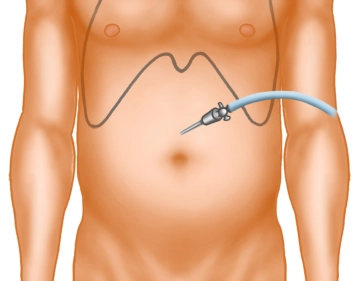

Ein kleiner Hautschnitt erfolgt deutlich oberhalb des Nabels in der Mittellinie. Nach Einführen der Verresnadel und Überprüfung der korrekten Lage wird das Pneumoperitoneum angelegt.

Hautinzision